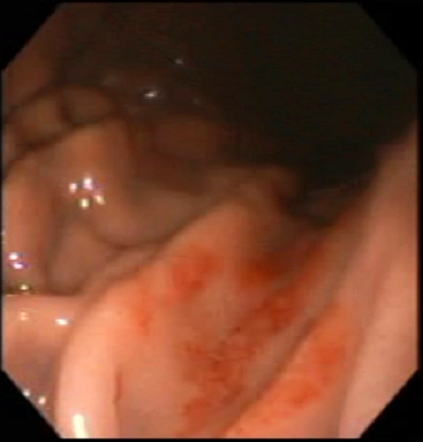

「タカダ医院」 胃カメラ検査 DVD写真

【胃潰瘍】

【胃 炎】

【胃 癌】